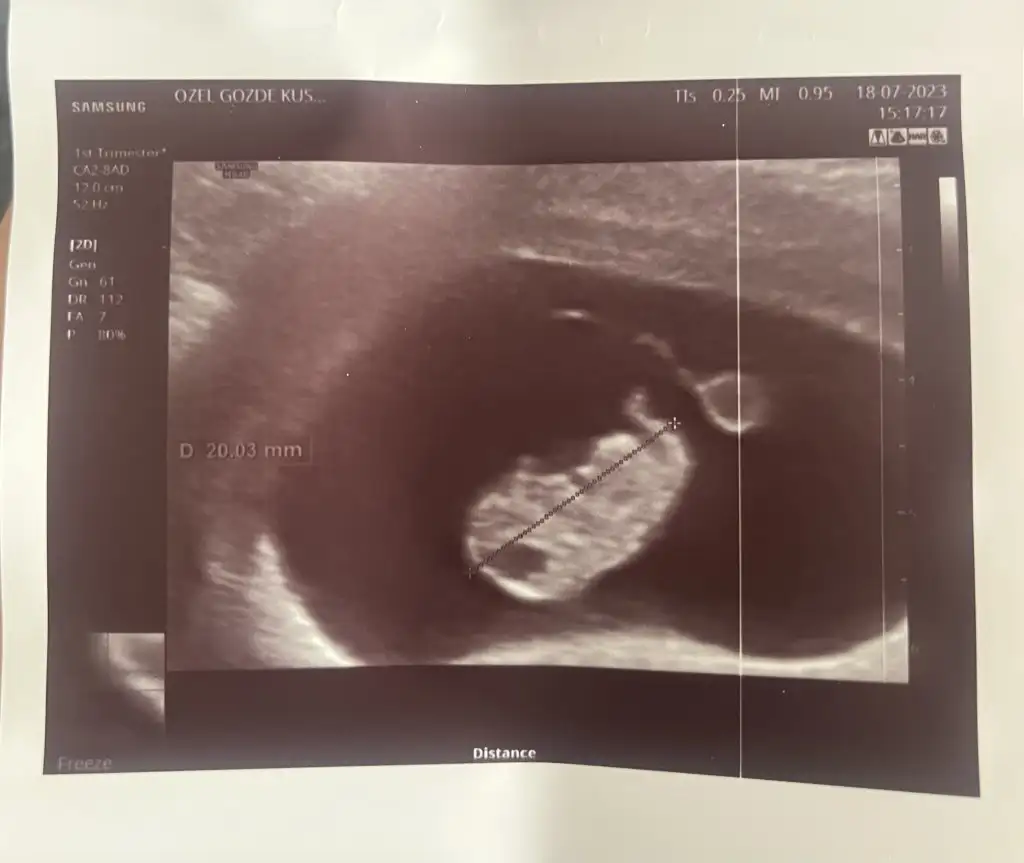

Ultrasona göre 8+5 bugün😅 ay ayağı var insana benziyor azıcıkkkk 🙈🙈 içim rahatladı sanki balonu var kenarda yolk saçı minnosumun 🥰

Şu kafasında niye boşluk var dedim orası yeni oluşuyor anatomik yapısı dedi bi korktum boş diye de anca oluşuyor dedi rahatladım 🤣🤣